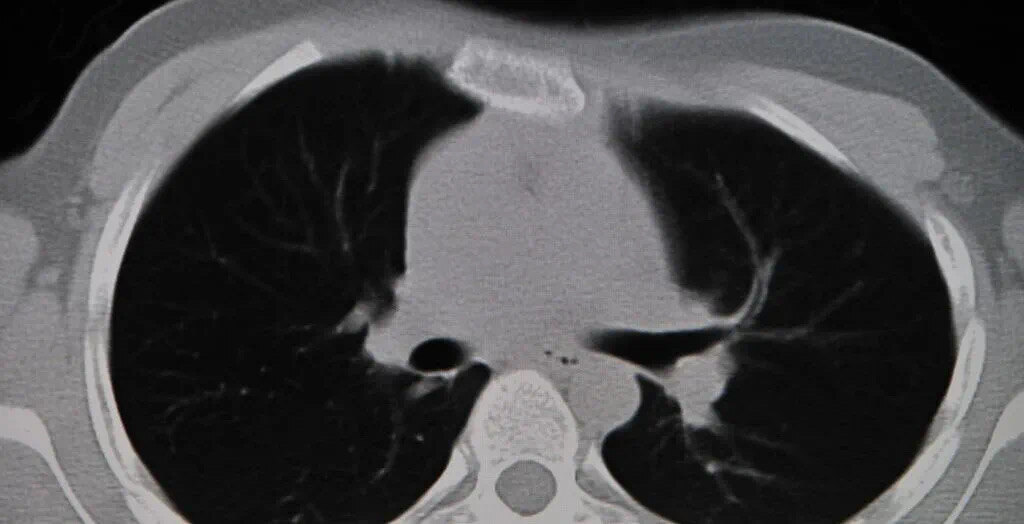

患有肺部小结节的人会在做x线或者ct检查时,发现肺部有一些阴影。肺炎、肺结核、肺不张等疾病都可能会引起肺部小结节。如果小结节的直径小于5mm是微小结节,小于1cm为小结节,大于3cm是肺部肿块,此时出现肺癌的可能性比较大。

肺部小结节主要分为两类,一类是炎性病变引起的,此时的肺部小结节不会太大,边缘是干净光滑的,它属于钙化结节,是一种良性的结节,一般不会发生癌变,但是也要注意定期复查。如果发现肺小结节的边缘呈菜花状,结节里有小水泡、血管,出现恶性的可能性很大。一旦确诊为肺癌,要及早进行手术切除。